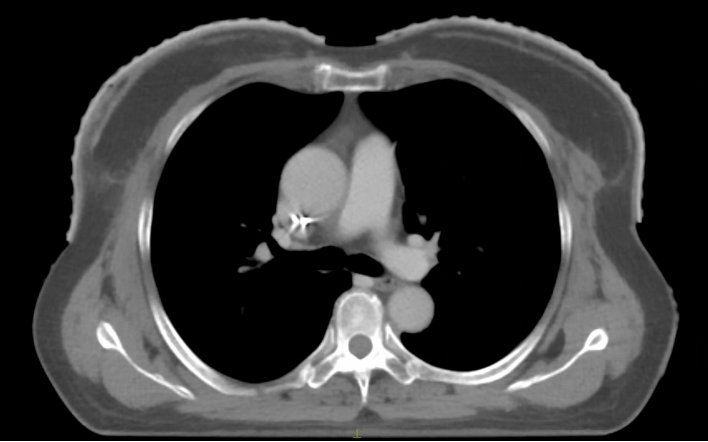

其次,为进一步降低心脏受照剂量,团队采用了深吸气屏气(DIBH)技术。通过训练,患者在深吸气状态下屏住呼吸,此时肺部扩张,心脏因生理解剖关系自然下移,远离放射区域,从而实现对心脏的“生理性保护”。这一主动屏气配合放疗,不仅显著降低了心脏辐射剂量,也减少了后期发生放射性心肌病、冠状动脉病变等并发症的风险。

DIBH技术:患者深吸一口气然后憋住,使胸廓和肺处于扩张状态,心脏移向后下方,心脏和肺组织主动“避开”高剂量辐射区照射。